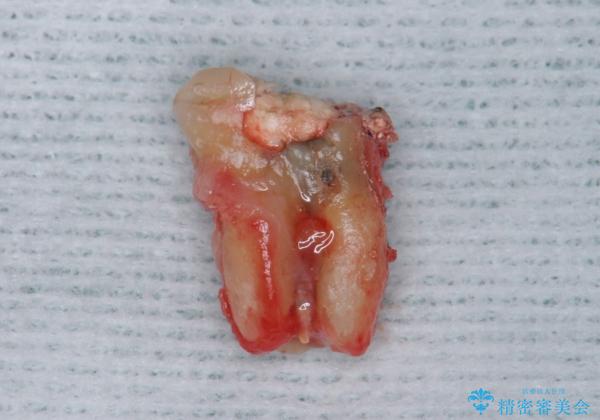

割れている奥歯を抜去後左上の機能していない親知らずを移植し、生着したのち根管治療・補綴を行いました。